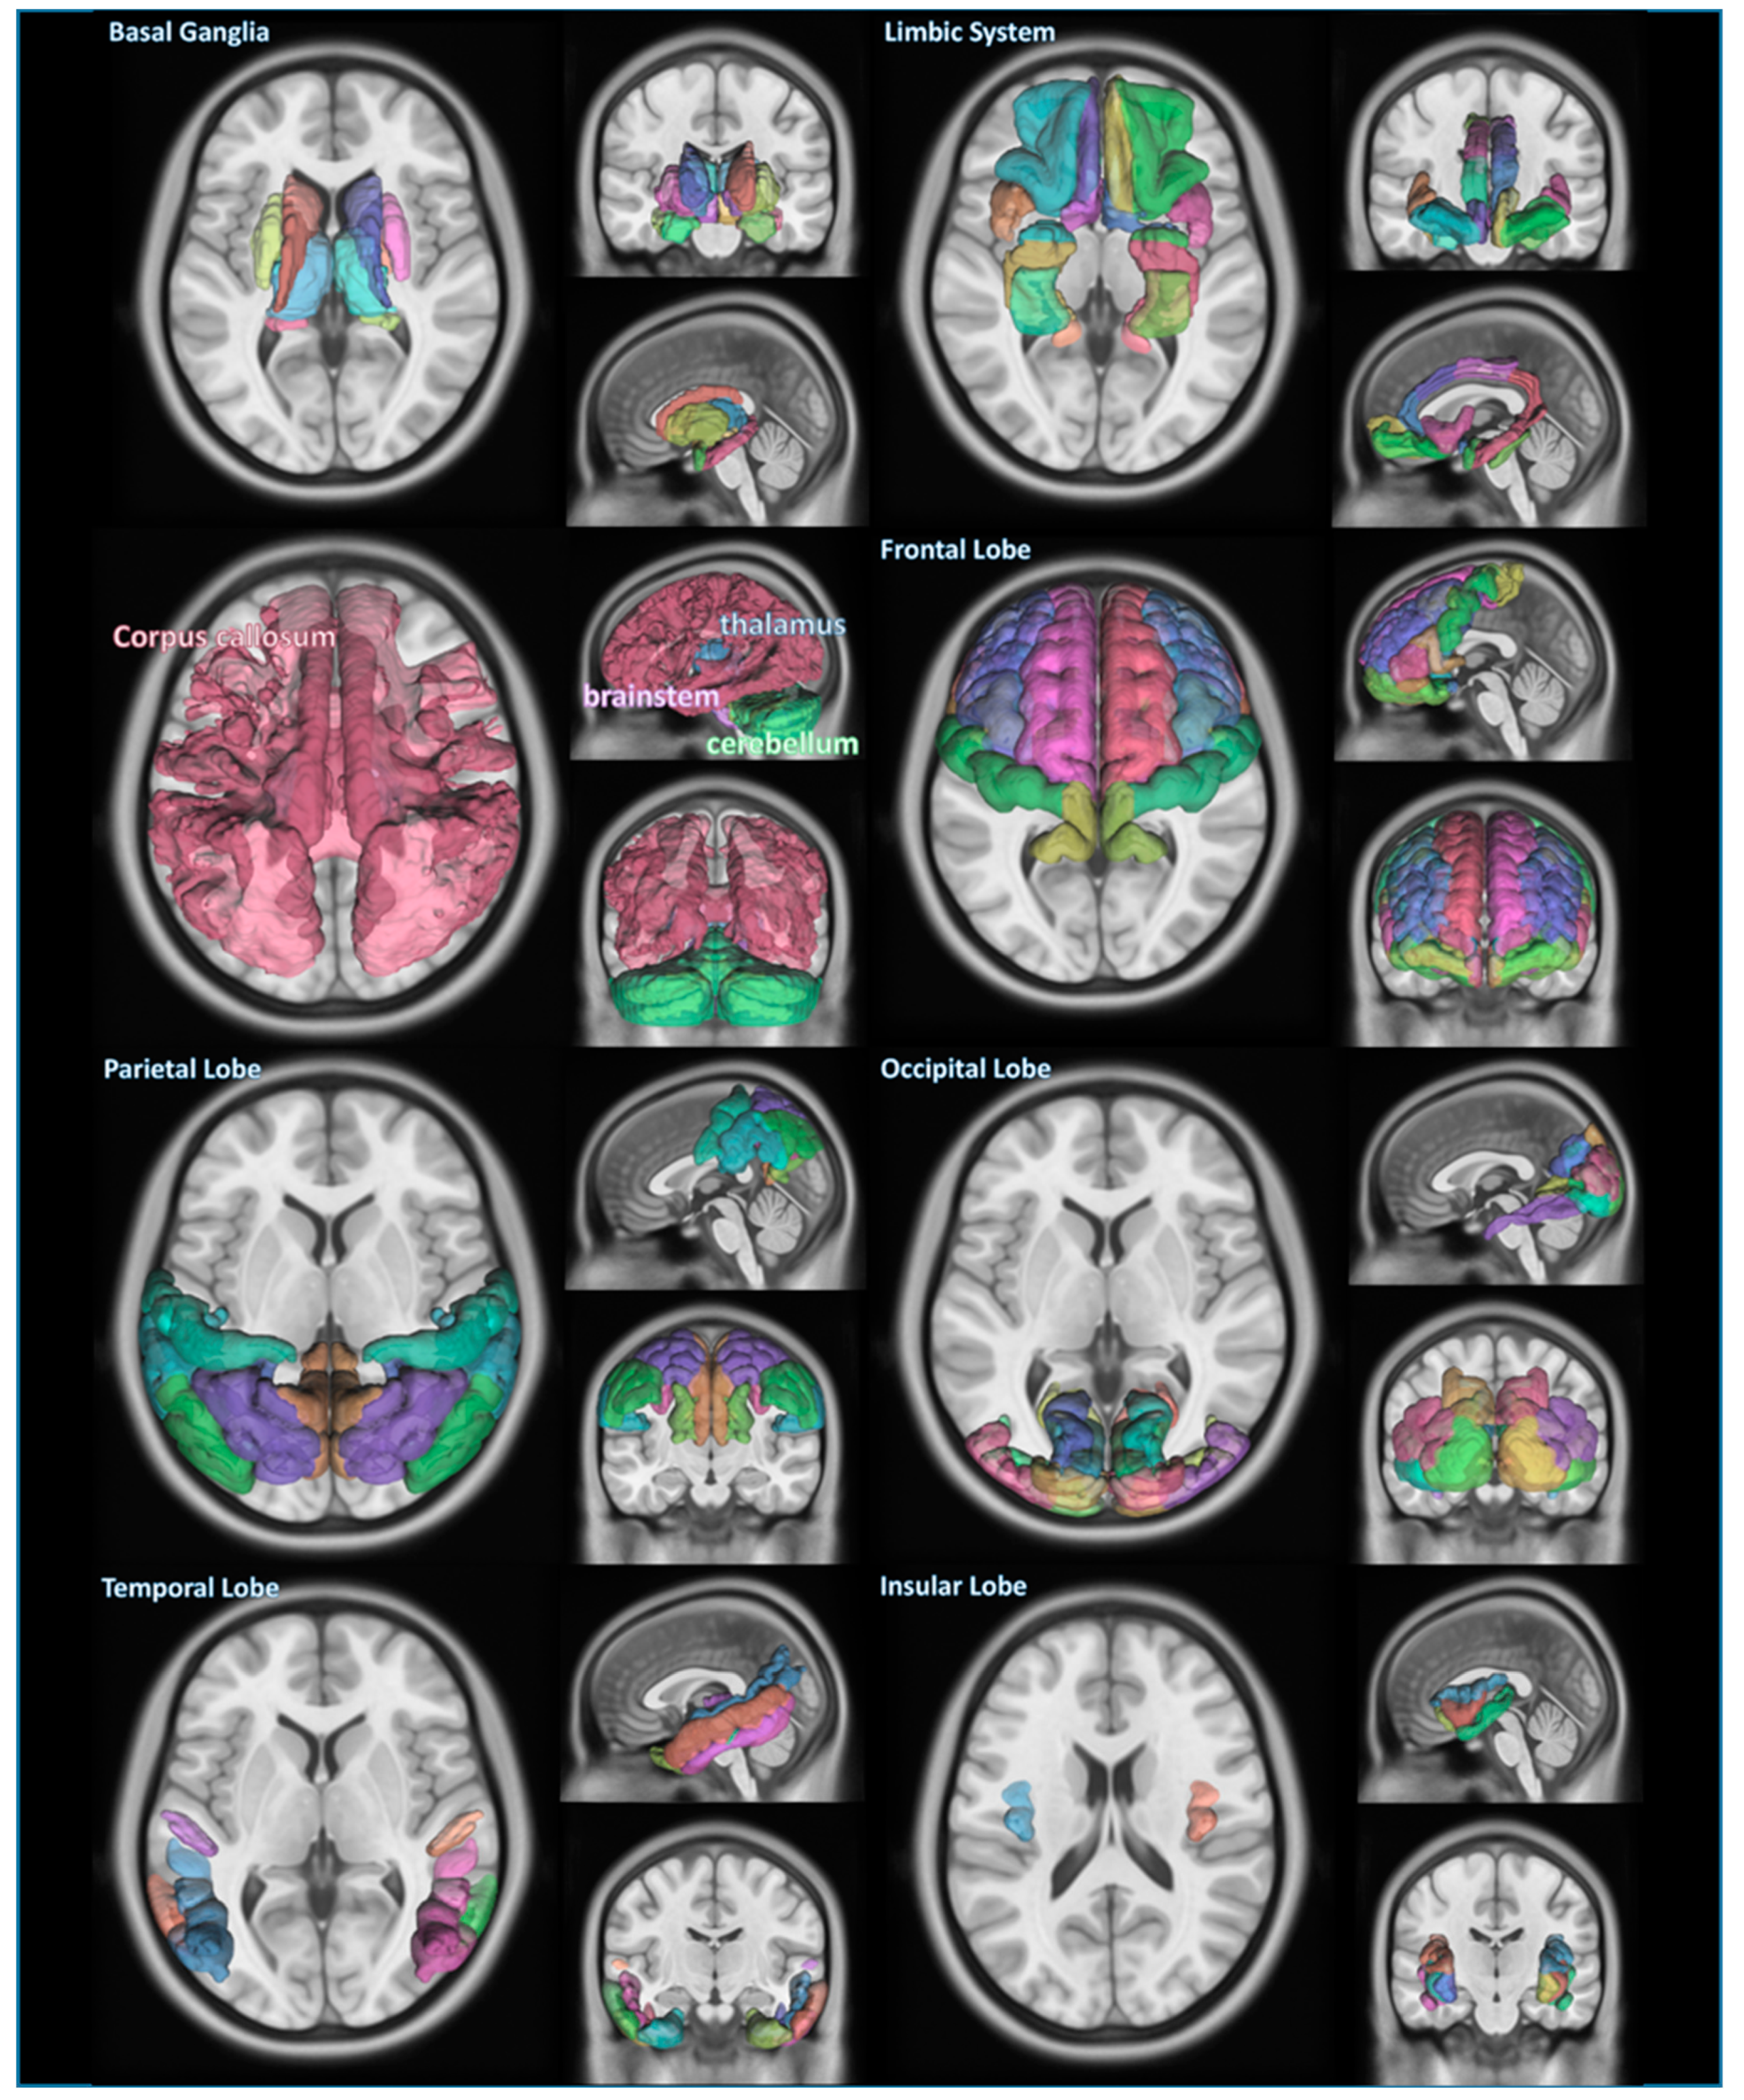

2.4. Classification of Brain Structures